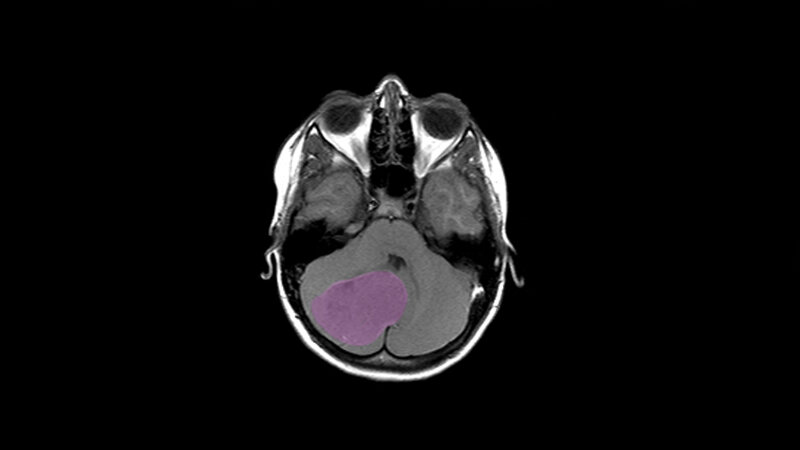

Medulloblastome sind bösartige Tumoren des Kleinhirns. Sie können in jedem Lebensalter vorkommen, meistens jedoch treten sie bei Kindern auf. Der Begriff Medulloblastom umfasst vier molekularbiologisch definierte Untergruppen, die mit sehr unterschiedlichen Krankheitsverläufen und Heilungschancen einhergehen. Kinder erkranken besonders häufig an Tumoren der Gruppen 3 und 4, die bislang wenig verstanden sind. Die Behandlung von Tumoren dieser Gruppe ist daher häufig schwierig. „Selbst wenn die Patienten gut auf die Behandlung ansprechen, werden sie oft zu einem hohen Preis geheilt, da sich die Therapie negativ auf das Gehirn, den IQ und die weitere Entwicklung der Kinder auswirken kann“, gibt Stefan Pfister, Wissenschaftler am Deutsches Krebsforschungszentrum, Oberarzt am Universitätsklinikum Heidelberg und Direktor am Hopp-Kindertumorzentrum am NCT Heidelberg (KiTZ), zu bedenken.

Unter Federführung von Wissenschaftlern aus dem DKFZ analysierte nun ein internationales Forscherteam knapp 500 Medulloblastome. Dabei stellten sie fest, dass die Hirntumoren genetisch weit vielfältiger sind als angenommen. Insbesondere in den Gruppen 3 und 4 waren mehr als die Hälfte der zugrundeliegenden genetischen Veränderungen bislang gänzlich unbekannt. „Während wir hier vorher gerade mal 30 Prozent der Tumoren molekularbiologisch erklären konnten, sind es jetzt 80 Prozent“, betont Peter Lichter, DKFZ.